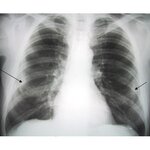

Posterior-anterior view of the chest with "en face" pleural changes in the mid zones on the right and left (arrows)

From the personal collection of Kenneth D. Rosenman MD